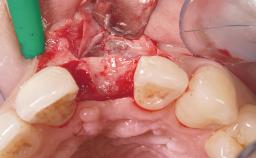

A 33-year-old female patient presented with an upper left central incisor that required extraction after a failed endodontic therapy. The tooth had been traumatized when the patient was a teenager and had undergone several endodontic treatments, including two apicectomy procedures. The patient was in good health and did not smoke. Clinical examination showed that the patient had a high lip line. In full smile, the gingival margins of the upper teeth were visible to the first molars. The gingival margins of central incisors 11 and 21 were only just showing. Examination of tooth 21 confirmed that the tooth was mobile and had hypererupted by 1 mm.

Socket Integrity Damage to one or more bone walls

Bone Volume Damage to one or more socket walls